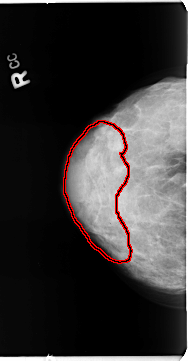

B_3112_1.RIGHT_CC

RIGHT_CC LINES 4688 PIXELS_PER_LINE 2432 BITS_PER_PIXEL 12 RESOLUTION 50 OVERLAY

FILE: B_3112_1.RIGHT_CC.OVERLAY

TOTAL_ABNORMALITIES 1

ABNORMALITY 1

LESION_TYPE CALCIFICATION TYPE PLEOMORPHIC DISTRIBUTION REGIONAL

ASSESSMENT 4

SUBTLETY 3

PATHOLOGY BENIGN

TOTAL_OUTLINES 1

BOUNDARY